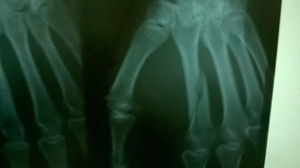

Все равно пошел в травму (травмпункт дзержинского района в ГКБ №2), на снимке - косой перелом второй пястной кости. Мне показалось, что со смещением, врач сказал: нормально, остность сохранена, все зарастет. Привязывают лангету, отпускают.

И вот я иду на очередной плановый рентген (рентгенкабинет на пр. Дзержинского, 15), мне выдают снимок с описанием, в описании сказано: "Слабо консолидированный косой перелом 2 пястной кости со смещением на ширину кортикального слоя". Иду к врачу Круппа в ГКБ№2, он опять мне говорит, что все нормально, мол на шишку в кисти не обращай внимания, все заживет. На вопрос: "почему за месяц не зажило" (перелом слабо сросшийся) говорит: еще две недели походи в гипсе, и все будет нормально, ну, шишка у тебя останется.

Конкретно тот, который я выложил, сделан через 27 дней после травмы. Есть еще два, самый первый через 7 дней после травмы, и последний через 35 дней после травмы.